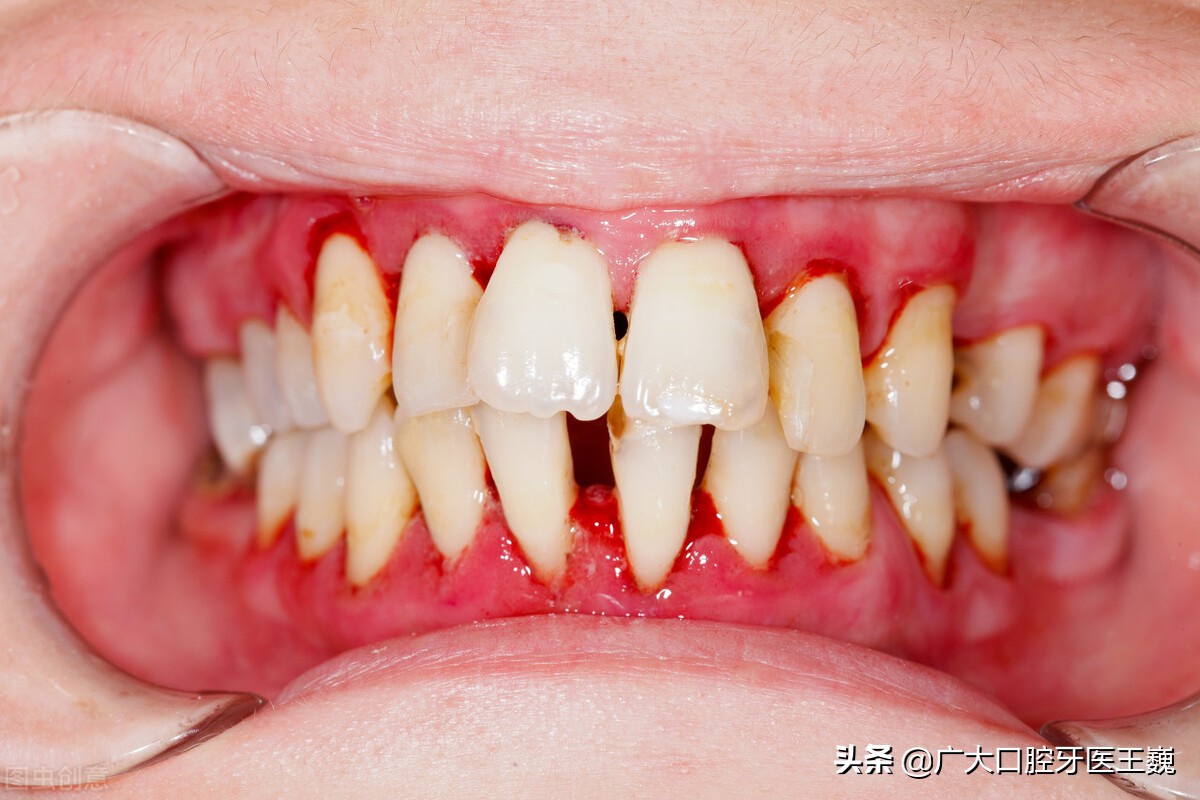

3、牙龈炎引起的疼痛

临床上牙龈炎的疼痛症状一般会表现为牙龈肿痛、出血。

出现这种情况大家可以在医生建议下对牙龈周围进行冲洗外用碘甘油控制炎症,后期就要清淡饮食,掌握正确的刷牙办法,如果一段时间后仍未控制解决,应及时到正规的口腔医院进行治疗。